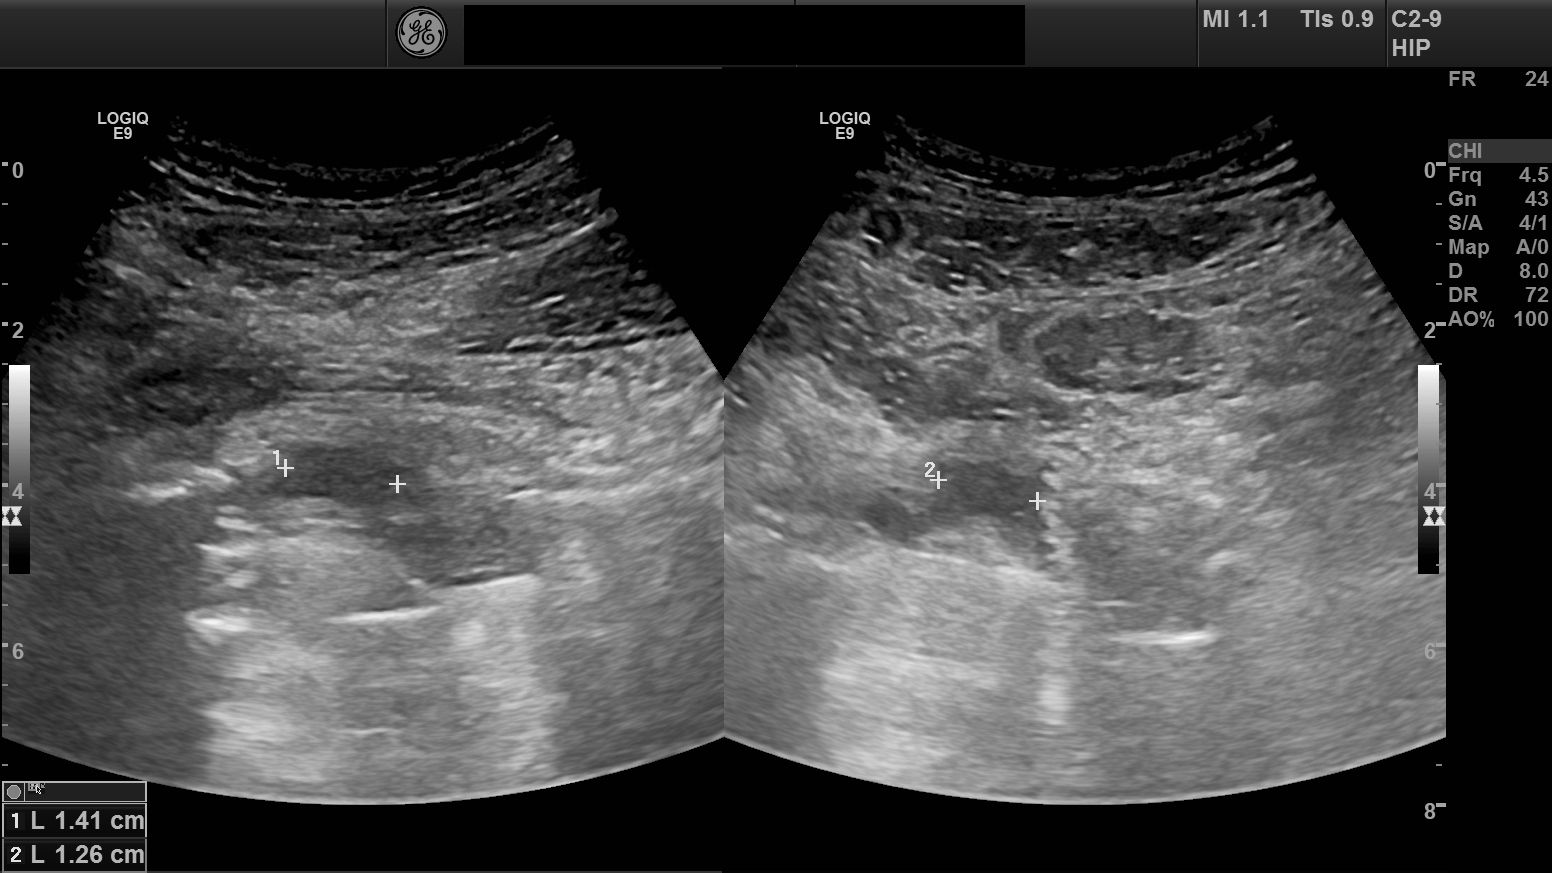

Patient who is referring to Specialist Center due to stiffness and ache about 4 months after plastic surgery of the hip. Plain X-rays are clear.

Niklas Norlén Ultrasound Specialist finds with ultrasound a gangion located anterior to the hip joint. In dynamic examination, an obstruction appears that explains the stiffness of the hip.

Hip plastic gangion